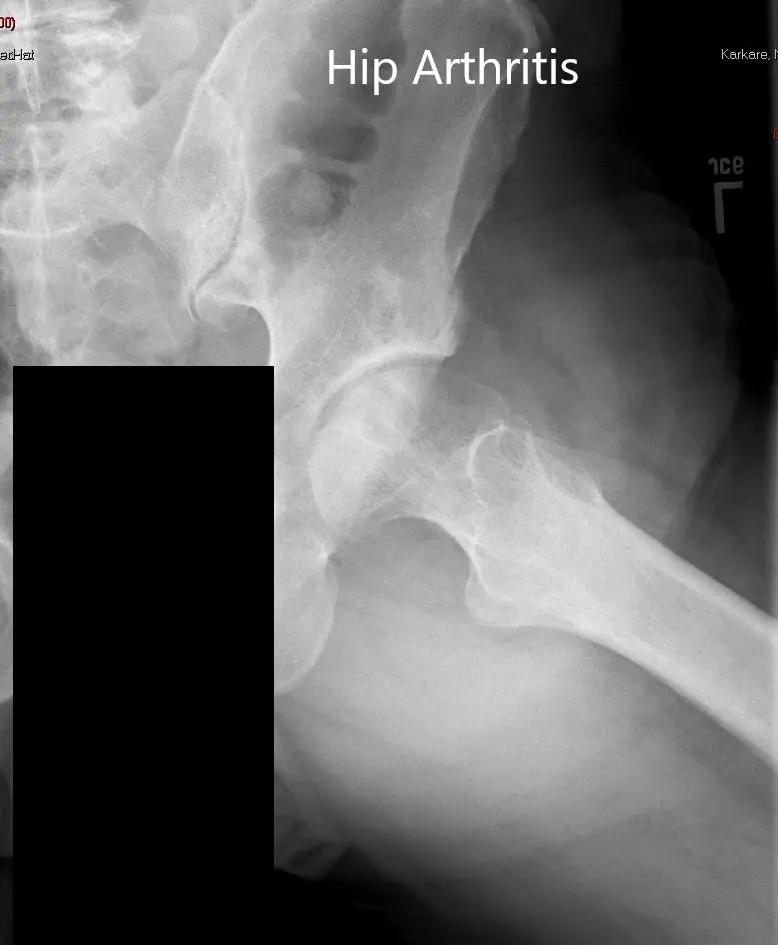

Imaging revealed severe osteoarthritis of the left hip with subchondral cysts, sclerosis, and osteophytes. The left acetabulum was shallow with a shortened left femoral neck.

Preoperative X-ray of the pelvis showing AP view of the pelvis with both hips.

Preoperative X-ray of the left hip in AP and frog-legged lateral views.